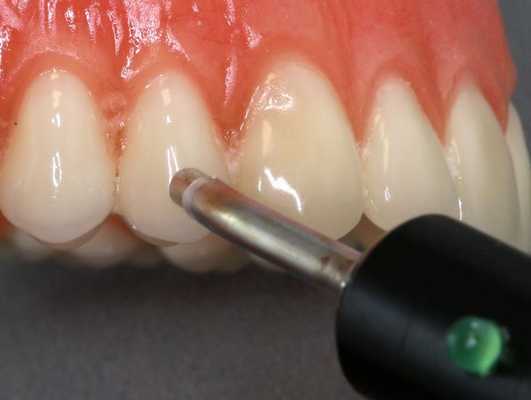

- ЭОД. С целью уточнения диагноза используется метод электроодонтометрии. Порог возбудимости причинного зуба находится в диапазоне от 100 до 120 мкА, что соответствует некрозу пульпы.

ЭОМ — это метод стоматологического исследования, основанный на определении порогового возбуждения болевых и тактильных рецепторов пульпы зуба при прохождении через неё электрического тока.